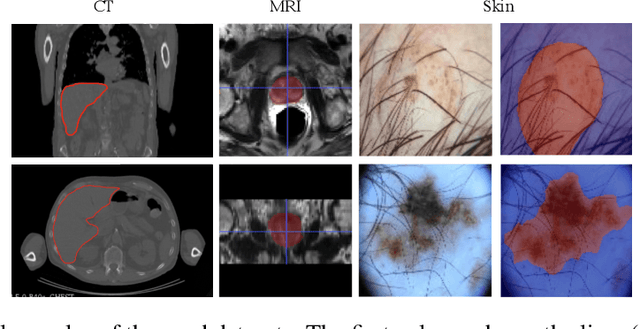

Skip connections in deep networks have improved both segmentation and classification performance by facilitating the training of deeper network architectures, and reducing the risks for vanishing gradients. They equip encoder-decoder-like networks with richer feature representations, but at the cost of higher memory usage, computation, and possibly resulting in transferring non-discriminative feature maps. In this paper, we focus on improving skip connections used in segmentation networks (e.g., U-Net, V-Net, and The One Hundred Layers Tiramisu (DensNet) architectures). We propose light, learnable skip connections which learn to first select the most discriminative channels and then attend to the most discriminative regions of the selected feature maps. The output of the proposed skip connections is a unique feature map which not only reduces the memory usage and network parameters to a high extent, but also improves segmentation accuracy. We evaluate the proposed method on three different 2D and volumetric datasets and demonstrate that the proposed light, learnable skip connections can outperform the traditional heavy skip connections in terms of segmentation accuracy, memory usage, and number of network parameters.